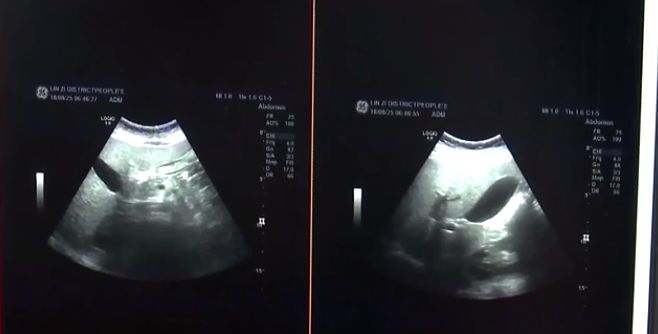

医生:“他当时并没有像成人脂肪肝表现出恶心、厌油、食欲下降等一些典型的表现,当时是我们通过化验血做超生才发现了脂肪肝的情况,所以说儿童脂肪肝的早期表现是很不典型的,需要我们家长早期提高警惕。”

此外,对于家有小胖墩的大人,最好每年定期做肝功能检查和肝脏B超,来排除脂肪肝隐患。